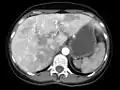

تشخیص تلانژکتازی با معاینه بالینی، لارنگوسکوپی و اندوسکوپی مقدور است. تشخیص ناهنجاریهای شریانی-وریدی نیز با روشهای مختلف تصویر برداری ممکن است.